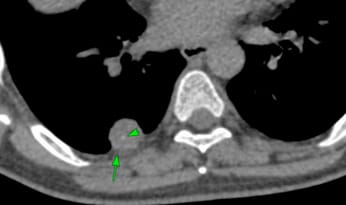

A 26-yrs old had progressive dyspnea. Echo showed severe pulmonary hypertension (PH). Her 4th CTPA was done a year later with us.

Her earlier 3 CTPAs over a year were reported as normal, except for the dilated MPA, RPA and LPA, with the first one erroneously diagnosing pulmonary thromboembolism.